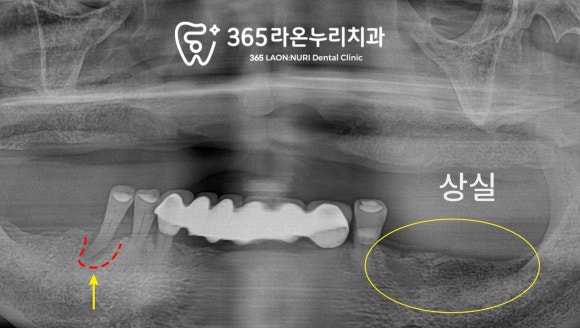

먼저 위쪽 사진인데요,

본인이 가지고 있는 치아가

모두 상실된 게 보이시죠?

그 때문에 틀니를 쓰고 계셔서

치조골의 두께가 조금 들쑥날쑥해 보이긴 합니다.

아래쪽 사진입니다.

어금니 부근이 없으셔서

앞니로만 식사를 하실 수 있는 상태네요.